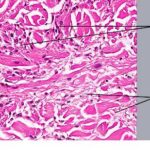

SUBCUTANEOUS TYPE The subcutaneous form of granuloma annulare occurs predominantly in children but is also described in adult patients. It is characterized by firm to hard, usually asymptomatic nodules located in the deep dermis and subcutaneous tissues. They may extend to underlying muscle, and nodules on the scalp and orbit are often adherent to the underlying periosteum. Individual lesions measure from 6 mm to 3.5 cm in diameter.They are distributed most often on the anterior lower legs in a pretibial location. Other sites of predilection are the ankles, dorsal feet, buttocks, and hands.93,95 Nodules on the scalp, eyelids,97-99 and orbital rim60,100,101 may present a diagnostic challenge. Subcutaneous granuloma annulare may also be found on the penis.102 PERFORATING TYPE The perforating type of granuloma annulare is a rare variant characterized by trans-epidermal elimination of the necrobiotic collagen. It may be localized, usually to the dorsal hands and fingers (see eFig. 43-3.1 in on-line edition), or generalized over the trunk and extremities. It has been described on the ears and within herpes zoster scars and tattoos. Superficial small papules develop central umbilication or crusting, and there may be discharge of a creamy fluid. Lesions heal with atrophic or hyperpigmented scars. In one series, 24 percent of patients complained of pruritus and 21 percent of pain.Papular umbilicated granuloma annulare on the hands of children and a generalized follicular pustular type of granuloma annulare85 may be clinical variants. PATCH TYPE Macular lesions that present as erythematous, red-brown, or violaceous patches without an annular rim are reported in adult women.An arcuate dermal erythema is also observed. Generalized confluent erythema has been described in an HIV-positive patient. Related Physical Findings Most patients with granuloma annulare are healthy and have no other abnormal physical findings. Arthralgia is reported in association with painful lesions on the hands. Granuloma annulare-like skin lesions and joint disease characterize a multisystem disorder described as interstitial granulomatous dermatitis with arthritis. Oral involvement was observed in one patient with HIV-associated disease. LABORATORY TESTS A diagnosis of localized annular granuloma annulare is made on clinical examination, and further evaluation is rarely indicated. Biopsy to obtain a specimen for histopathologic examination is necessary when the presentation is atypical, when lesions are symptomatic, and when the diagnosis is otherwise in doubt. Histopathologic analysis may be required to confirm a diagnosis of generalized granuloma annulare or subcutaneous nodular disease on the head and orbital region. Histopathologic Findings The diagnosis is best made at low magnification. Changes are usually observed in the upper and middle dermis, although any part of the dermis or subcutis can be involved. The characteristic histopathologic finding is a lymphohistiocytic granuloma associated with varying degrees of connective tissue degeneration and mucin deposition. The inflammatory infiltrate may have a palisaded or interstitial pattern, or a mixture of both patterns.Occasionally, a sarcoid-like pattern with large epithelioid histiocytes is seen. The typical appearance is of single or multiple foci of inflammation with a central core of altered collagen (necrobiosis) surrounded by a wall of palisaded histiocytes . The necrobiotic centers are usually oval, slightly basophilic, devoid of nuclei, and marked by a loss of definition of the collagen bundles and diminished or absent elastic tissue fibers. Stains for mucin and lipid often give positive results. Differential Diagnosis of Granuloma Annulare ANNULAR TYPE Consider